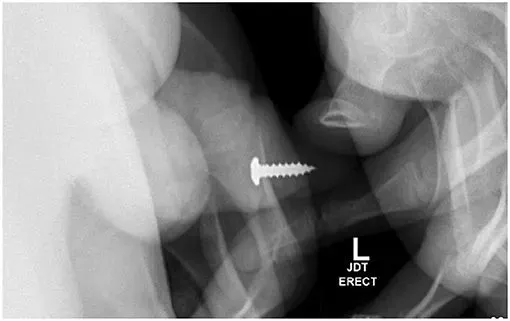

Benda pertama yang dimasukkan ke dalam uretra adalah sebuah paku. Pasien dibawa ke ruang operasi dan diberikan anestesi umum, dan benda asing tersebut dikeluarkan menggunakan sistoskop 19fr dan penjepit fleksibel.

Diketahui, remaja tersebut memiliki riwayat kejiwaan yang signifikan. Beberapa bulan kemudian, ia datang dengan keluhan memasukkan sekrup logam sendiri ke dalam uretranya selain mengonsumsi hidroksizin.

Selama pemeriksaan ini, benda asing teraba di uretra penis distal dan ditemukan benda kedua yakni sekrup. Gejala utamanya berupa retensi urine dan nyeri penis.

Seorang remaja berusia 17 tahun memasukkan sekrup ke dalam uretranya sendiri. Tak hanya sekali, ia memasukkan total 20 kali hingga dilarikan ke UGD. Foto: Adam Bezinque/ jurnal Frontiers In

Sebuah sekrup ditempatkan di uretra distal dan diposisikan sedemikian rupa, sehingga ujung tumpulnya akan dikeluarkan terlebih dahulu. Tim medis pun melanjutkan penanganan observasional konservatif dengan uji coba berkemih agar pasien dapat mengeluarkan benda asing.